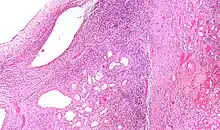

Micrograph of a cystic nephroma (left of image). Normal kidney is seen on the right. H&E stain. | |

A cystic nephroma, also known as multilocular cystic nephroma, mixed epithelial stromal tumour (MEST) and renal epithelial stromal tumour (REST),[1] is a type of rare benign kidney tumour.